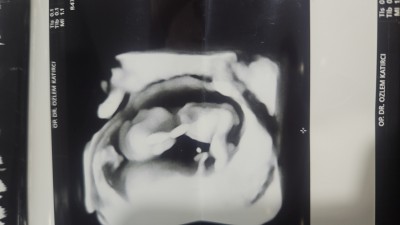

Kızlar merhaba 11 haftalik hamileyim. Kontrolde doktor kararsız kaldım önce kız gibi geldi ama şuan da erkeğe benzettim dedi. Bir daha bakiyim dedim erkek gibi görünüyor 1 ay sonra gel netleşir dedi. Fotoğraf yüklüyorum sizce ?

Cnm bu erkek yüzde 80

Erkek canım içimden geçti sağlıkla kucağına al inşallah